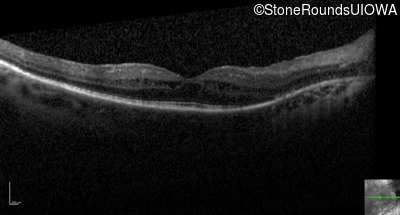

Optical Coherence Tomography - Right - 20/32

Exemplar / OCT Stack

OCT Stack